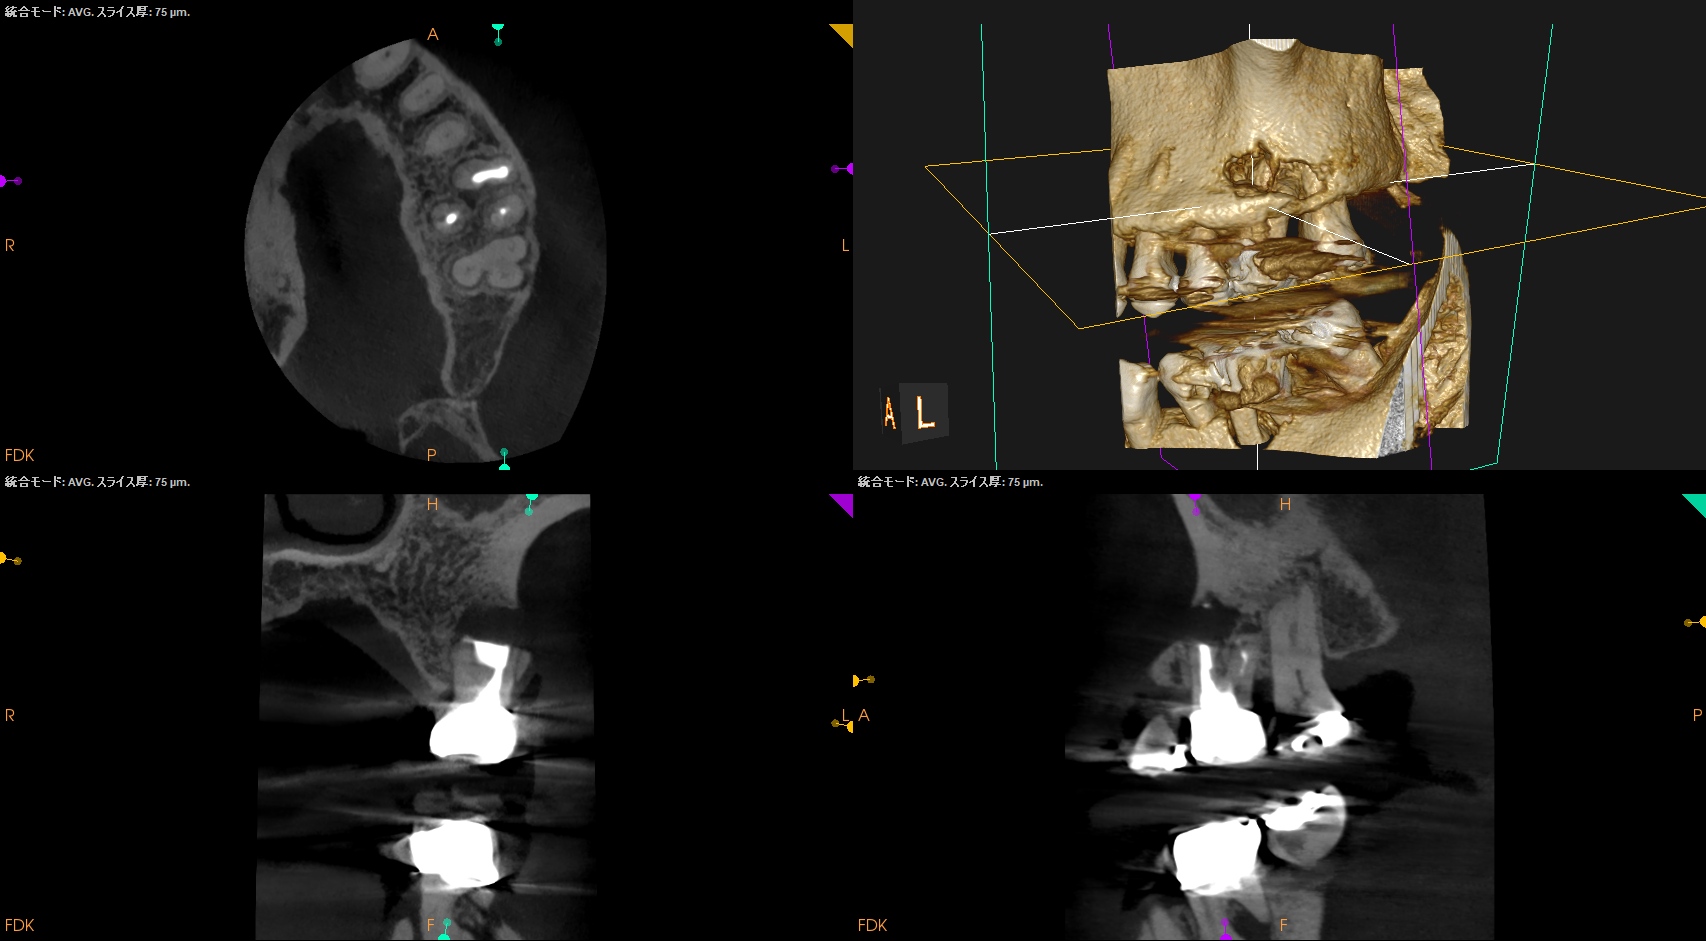

DBは楽だが、MBは頬舌径が7.4mmでMB1, MB2があるという…難ケースだ。

#14 MB,DB Apicoectomy(2026.2.12)

逆根充後にPA, CBCTを撮影した。